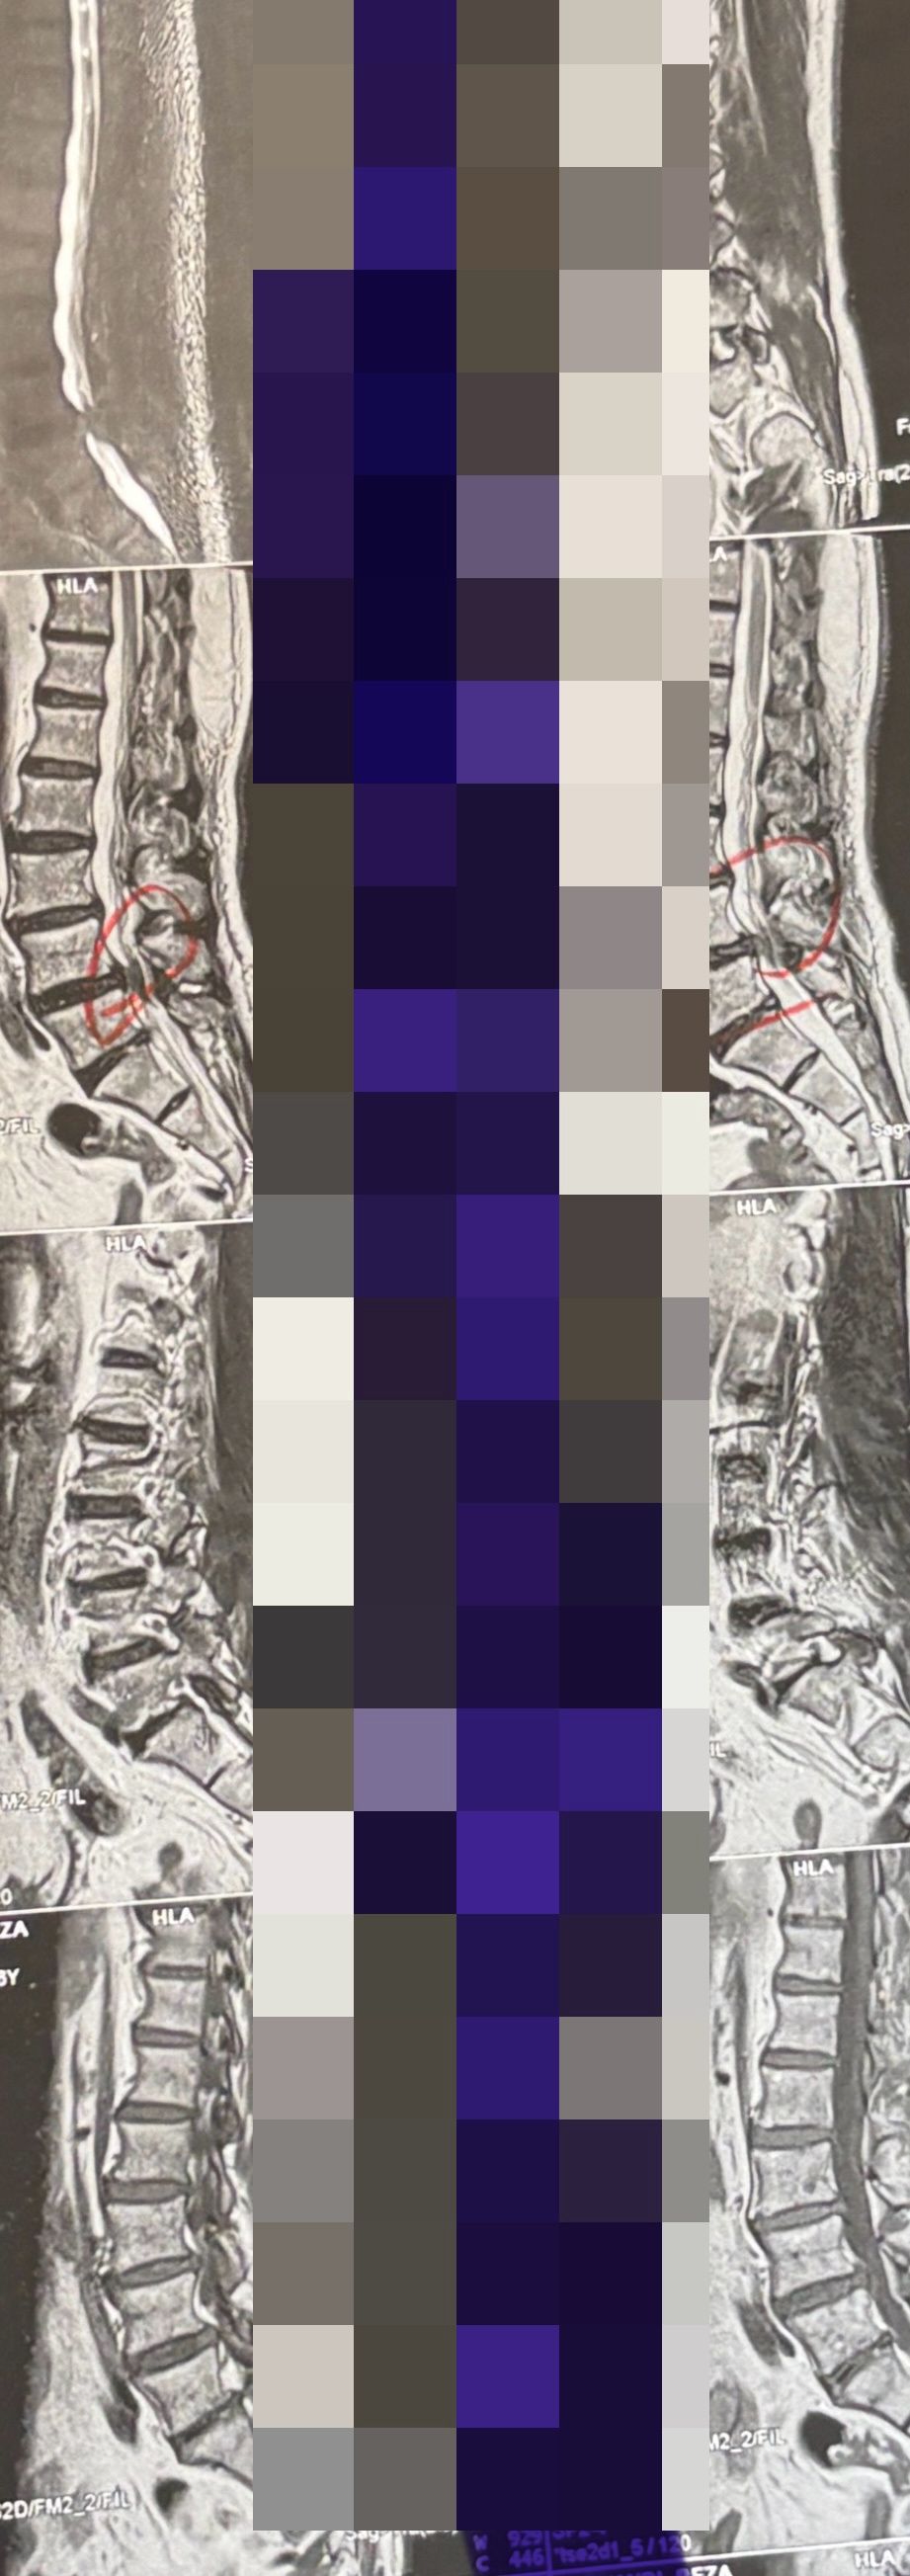

Case 1

30 year old patient of mine with R. IVF disc extrusion of C 5-6 with R upper extremity pain and numbness without neurological deficit was suggested to have urgent surgery

in his EMG. NCV didn’t have any active axonal loss

got 20 sessions of chiropractic care in one month by me mainly using decompression and C0-C1 prone drop manipulation and 3 sessions of mild adjustment to segments above disc herniation. No direct adjustment to the involved disc extrusion

After treatment:

reduction of R. IVFdisc extrusion by more than 50%.

90% improvement in patient’s signs and symptoms and preventing of unnecessary expensive surgery

following one month of cervical chiropractic spinal treatments